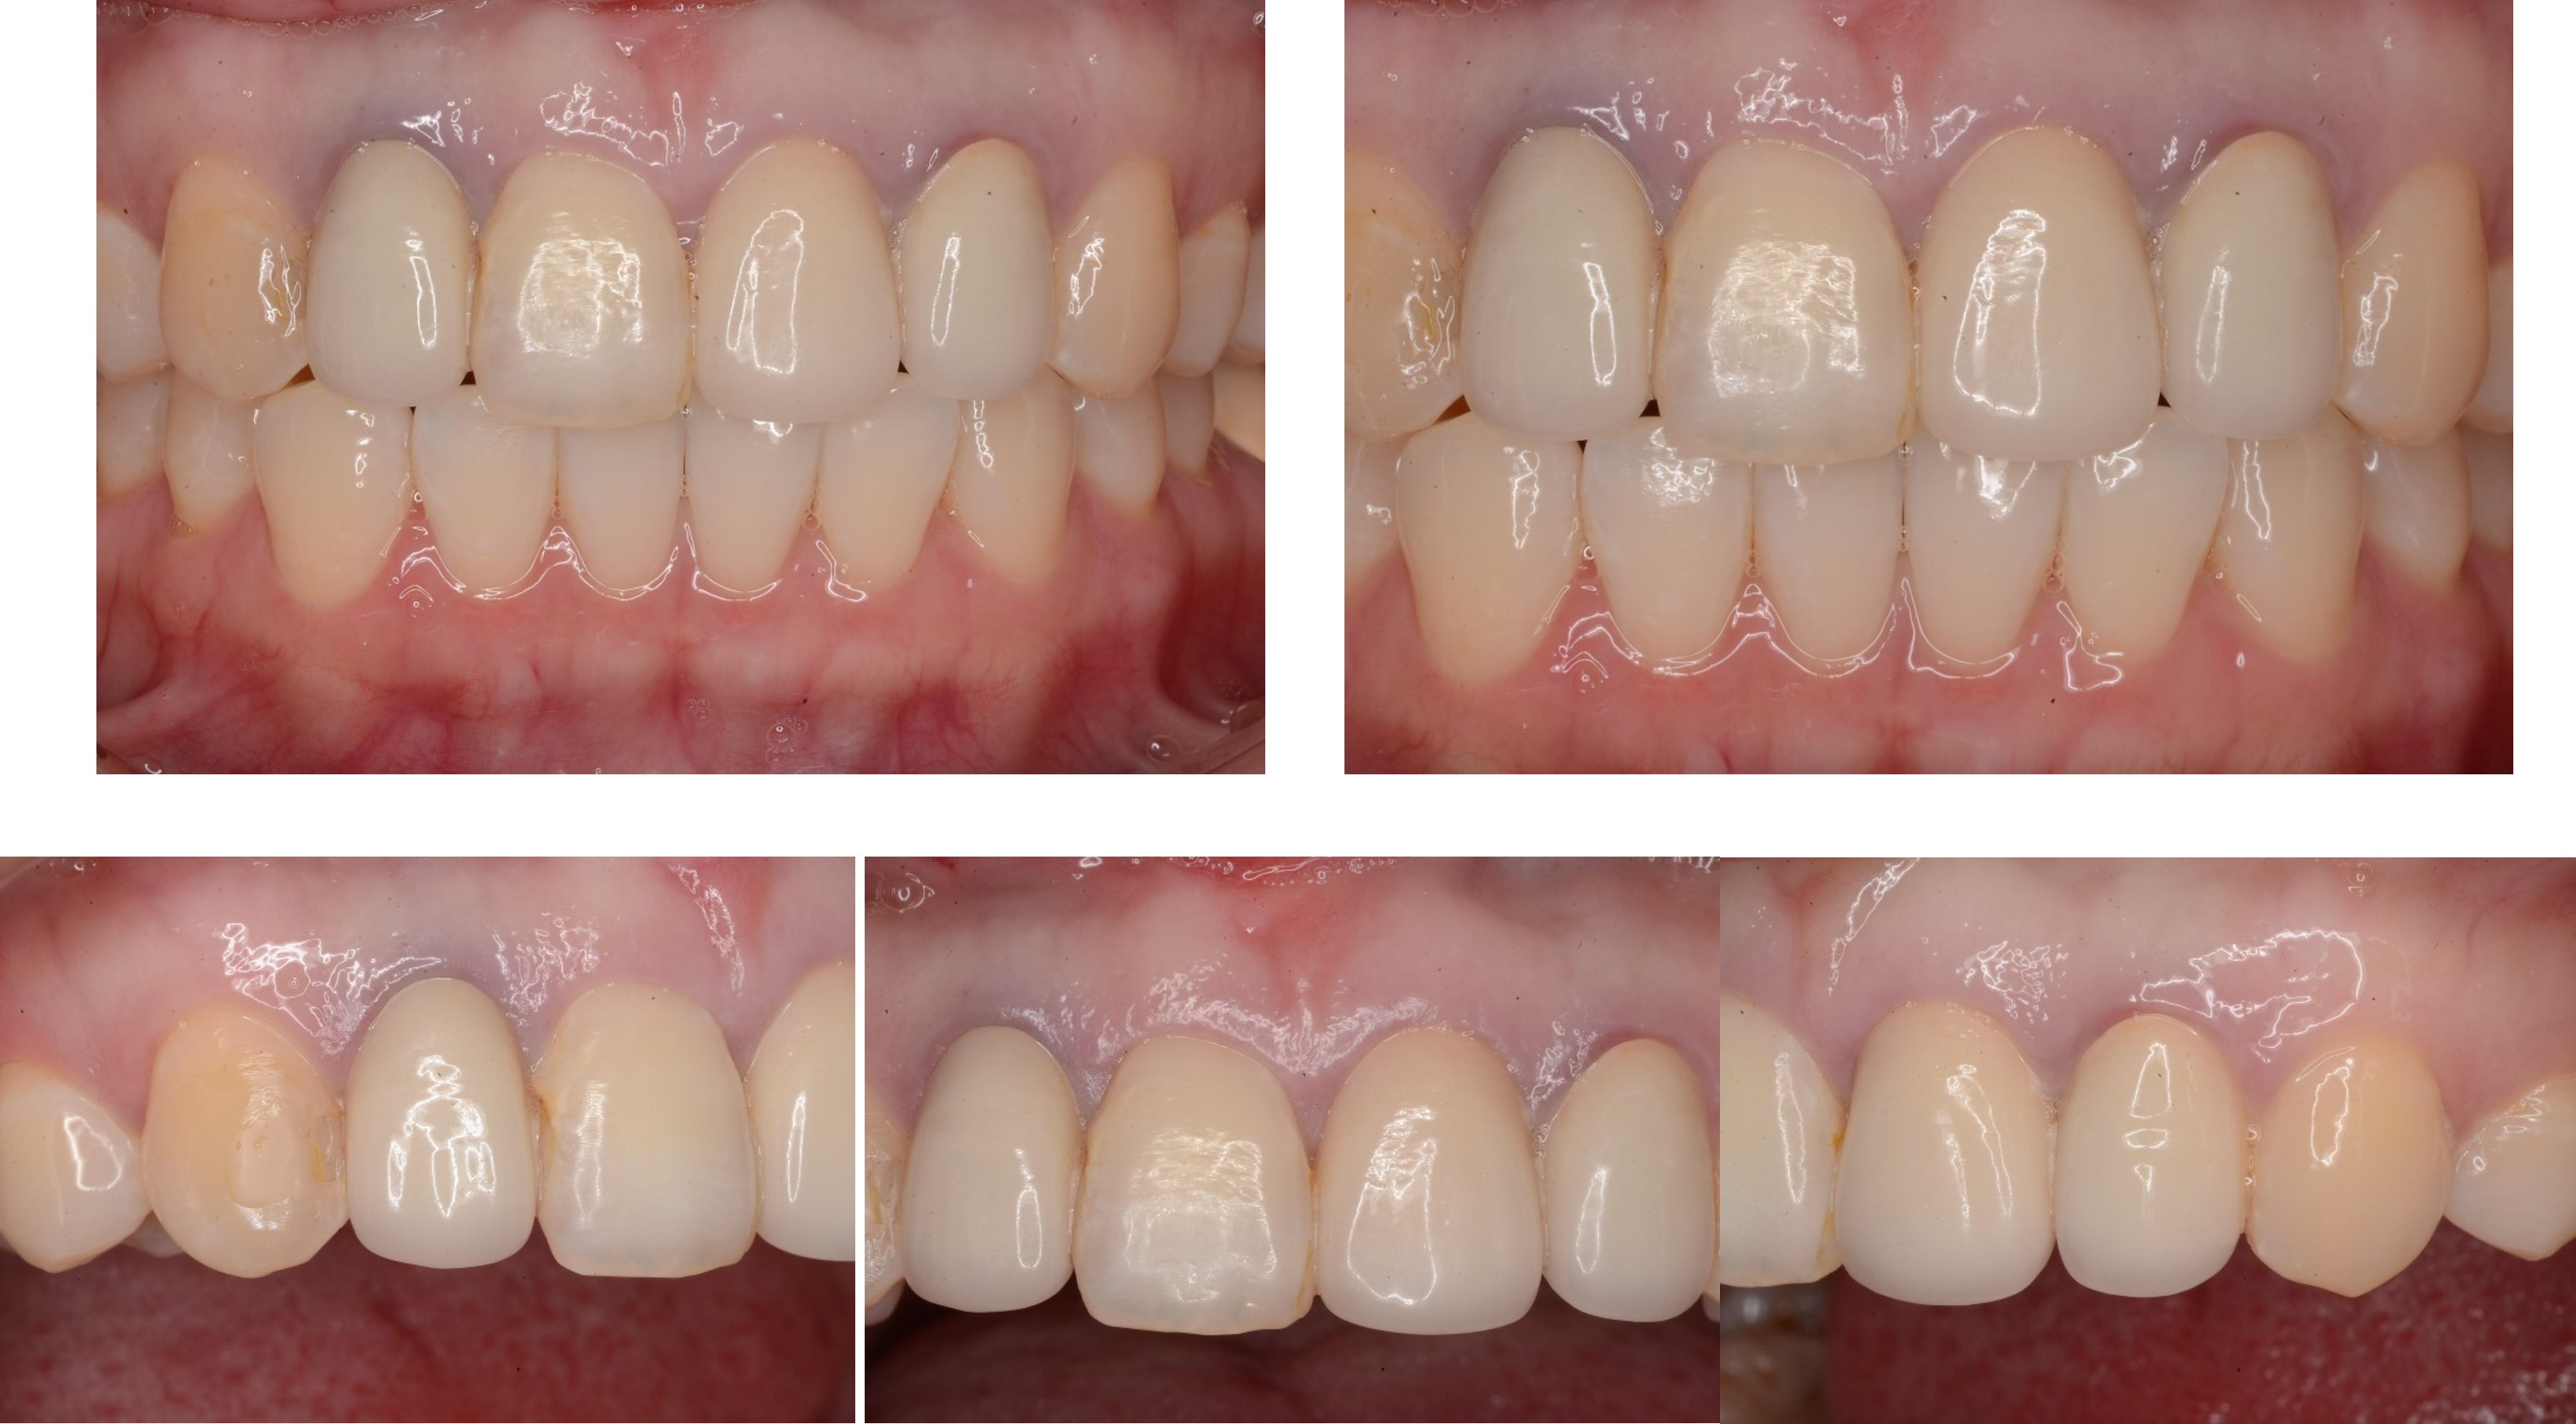

前牙全瓷冠

前牙美觀與功能兼顧

微笑時,患者開心

術前、術後比較